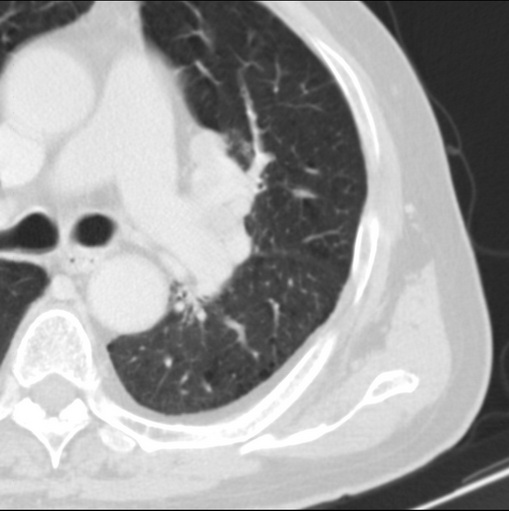

标题: CT25434:胸部CT增强扫描

男性患者 81岁 咳嗽 咳痰 咯血

左肺中心型肺癌并:1.左肺阻塞性肺炎;2.纵隔淋巴结肿大;

考虑左上肺癌并阻塞性肺炎,左肺转移、左肺门及纵隔淋巴结转移。

肿块贴近左肺门,包绕左上肺动脉,形态不规则。肿块增强扫描中度强化。纵膈内主动脉弓左旁间隙、气管隆突前、下间隙见多枚淋巴结影。综上考虑左侧中央型肺癌可能性大。图片没有完整上传,尤其是左肺上叶支气管分支层面没有上传,因此不好判断是叶支气管中断还是段支气管中断。另外,下图红色部分所示是“黏液支气管征”吗?